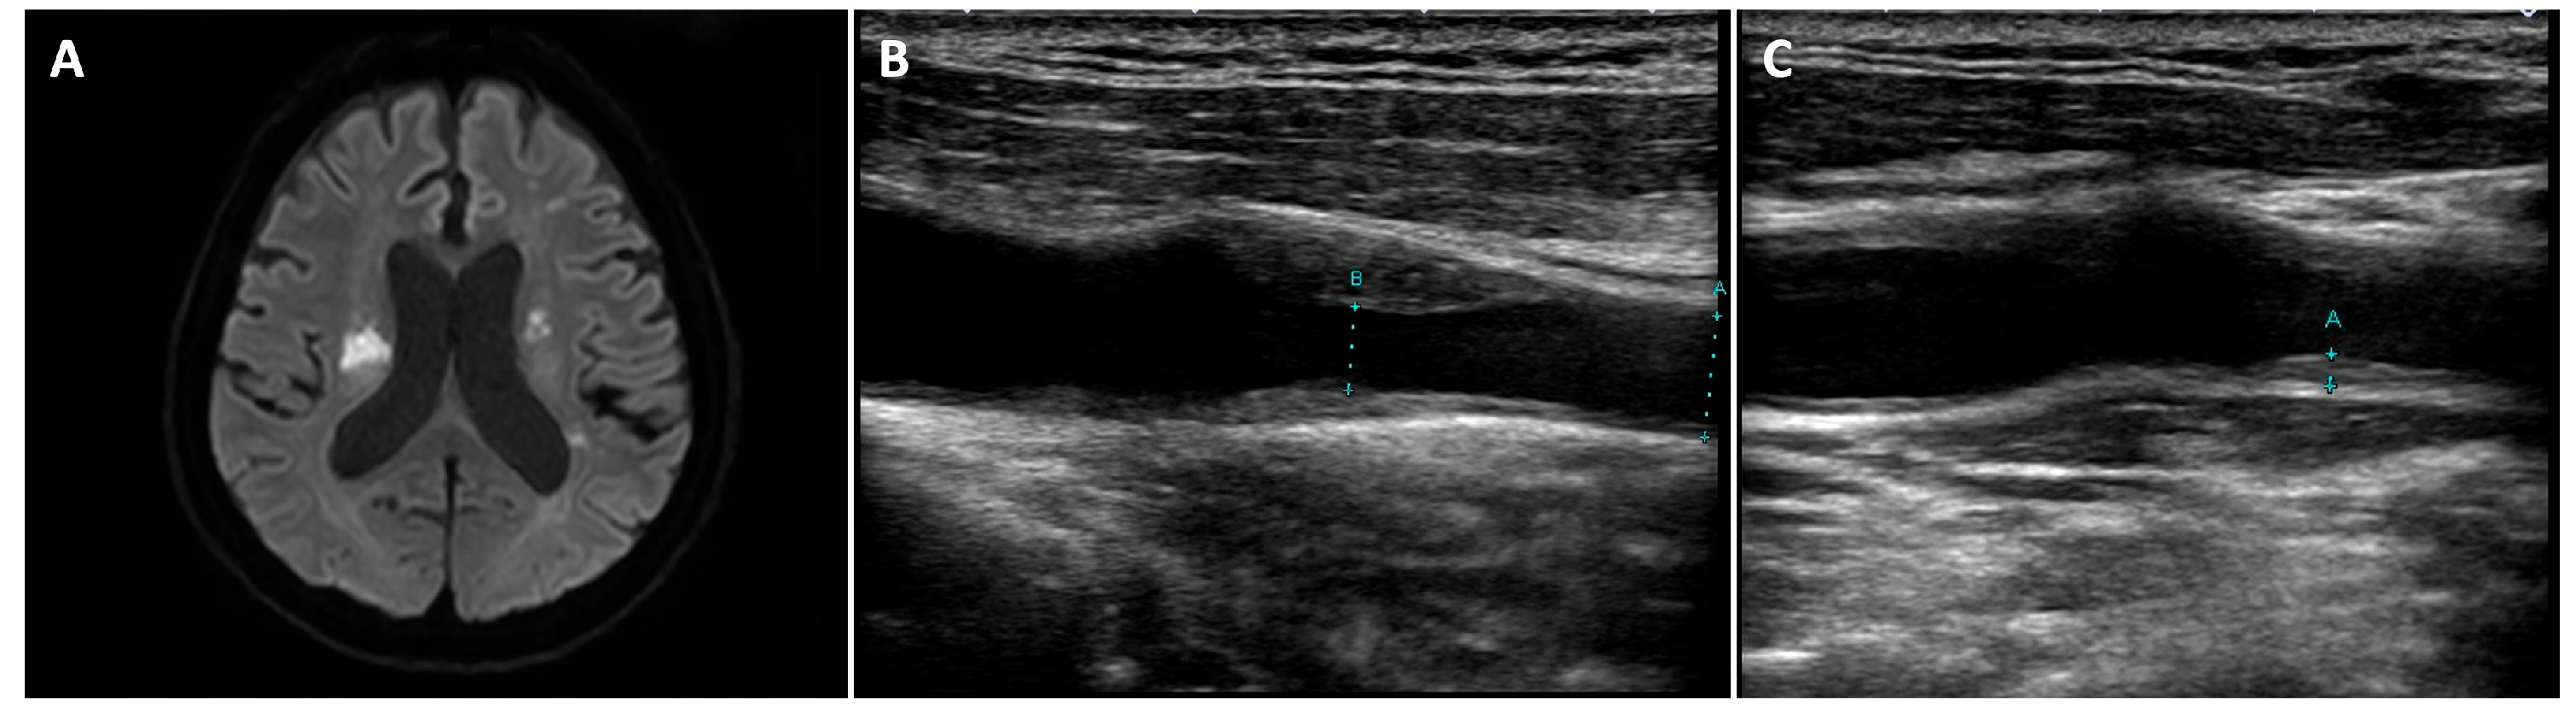

2. Case Presentation